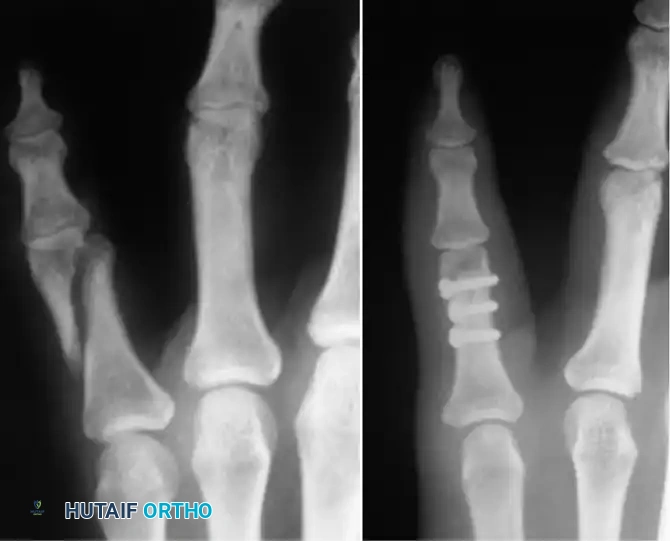

1. Intramedullary Kirschner Wire Fixation

For transverse or short oblique fractures, intramedullary K-wire fixation provides excellent axial alignment with minimal soft-tissue stripping.

Technique: Introduce a 0.062-inch K-wire at the fracture site. Drill it retrograde out through the skin at the metacarpal base. While drilling, force a slight bow in the wire (convex toward the palm) and hold the wrist in flexion so the wire emerges safely on the dorsum of the wrist. Reduce the fracture anatomically. Drill the wire anterograde into the distal fragment, stopping just proximal to the articular surface of the MCP joint. Cut the proximal end beneath the skin.

Fig. 64-37 Radiograph showing reduction and fi xation of fracture of metacarpal shaft and neck.

Alternatively, closed percutaneous pinning can be performed. With the MCP joint acutely flexed (to tighten the collateral ligaments and control the distal fragment), introduce a K-wire through the metacarpal head and advance it across the fracture site under fluoroscopic guidance.

2. Interfragmentary Screw Fixation

Long oblique or spiral fractures of the metacarpal shaft (where the fracture length is at least twice the diameter of the diaphysis) are ideally suited for interfragmentary lag screw fixation.

This technique provides absolute stability, allowing for immediate postoperative mobilization. It requires minimal periosteal stripping and avoids the hardware prominence associated with dorsal plating. Typically, two or three 1.5 mm or 2.0 mm cortical screws are utilized, placed perpendicular to the fracture plane to maximize compression.